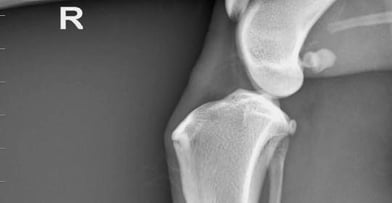

La diagnosi viene emessa sulla base dei rilievi della visita clinica; l’esame radiografico del ginocchio può aggiungere informazioni circa la conformazione dell’arto posteriore e lo stato dell’articolazione (presenza di osteofiti, aumento liquido articolare etc.)